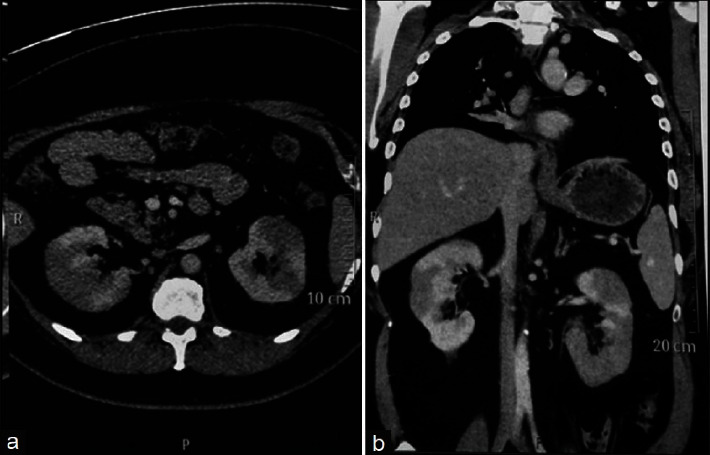

IgG4-related disease (IgG4-RD) is an immune-mediated disorder marked by fibro-inflammatory masses that can infiltrate multiple organ systems. Due to its relatively recent discovery and limited understanding of its pathophysiology, IgG4-related disease may be difficult to recognize and is consequently potentially underdiagnosed. Renal involvement is becoming regarded as one of the key features of this disease. To date, the most well-recognized renal complication of IgG4-related disease is tubulointerstitial nephritis, but membranous glomerulonephritis, renal masses, and retroperitoneal fibrosis have also been reported. This concise review has two objectives. First, it will briefly encapsulate the history, epidemiology, and presentation of IgG4-related disease. Second, it will examine the reported renal manifestations of IgG4-related disease, exploring the relevant histology, imaging, clinical features, and treatment considerations. This synthesis will be highly relevant for nephrologists, rheumatologists, general internists, and renal pathologists to raise awareness and help improve early recognition of IgG4-related kidney disease (IgG4-RKD).